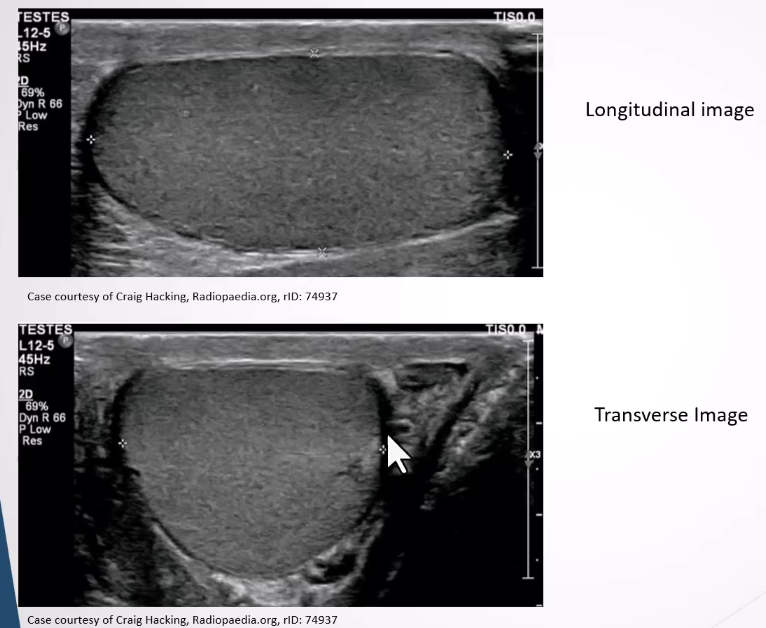

Testes:

Medium homogeneous appearance.

Tunica albuginea visible as a thin echogenic line surroudning the testes

Tunica invaginates to form a linear ehcogenic mediastinum testis

Rete testis may appear as a hypoechoic region near mediastinum and easily visible if dilated

Appnedix testis can be seen if combined with a hydrocele